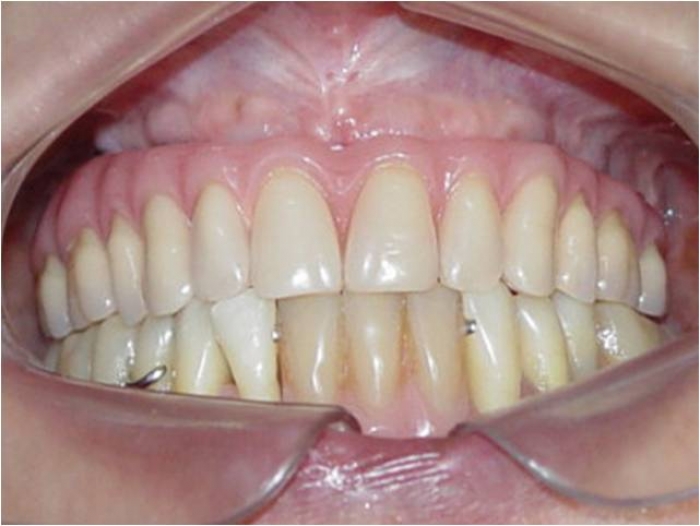

Prótese fixa em resina sobre implantes, do caso terminado em Dezembro de 2007

Sorriso final